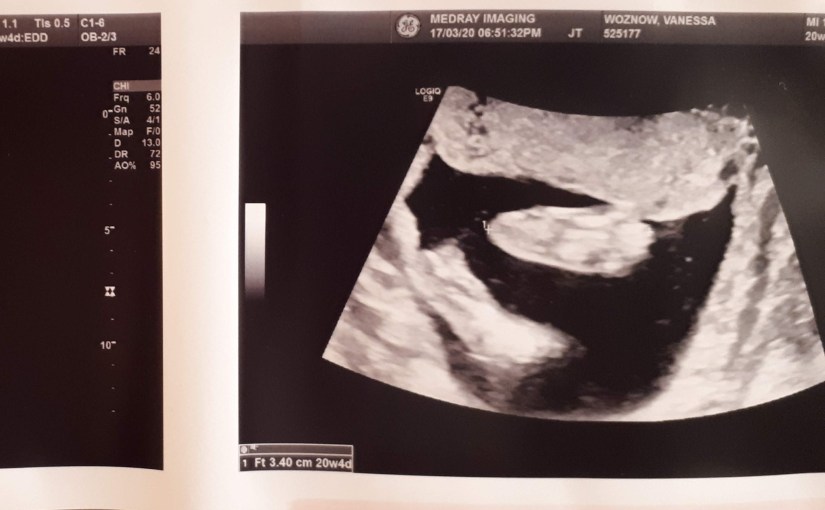

I’m also trying not to let it bother me that Marc isn’t allowed to come to anymore of my appointments.

My twenty-week ultrasound was yesterday, and he was relegated to the parking lot as I got to see and say hello to our little one.

It will be the same for our midwife appointment today, and all future meetings going forward.

I’ve been trying to get him to feel the little kicks that have slowly begun to get stronger over the past week, but sometimes I think the babe is a bit of a trickster because they will immediately stop moving as soon as he puts his hand on my tummy.

Even now as I write this, I can feel them dancing about. I think they may be saying hello.